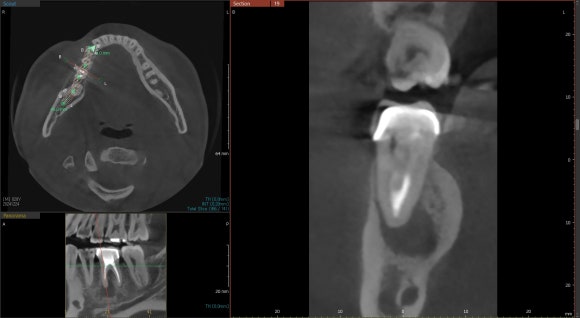

이때 CT는 아주 고마운 진단도구입니다.

이전 치료에서 놓친 것은 무엇인지,

염증의 정확한 위치와 크기는 어느정도인지

사전에 파악할 수 있게 도와줍니다.

따라서

재신경치료의 가능성 여부를

어느 정도 가늠할 수 있는 근거가 됩니다.

(상) 재신경치료 전 (하) 재신경치료 후

CT로 확인해보면 더욱 만족스럽습니다.

위 사진이 치료 전,

아래 사진이 치료 후 3개월 차에 촬영한

치아의 단면입니다.

거의 완치수준이라고 봐도 될것입니다.